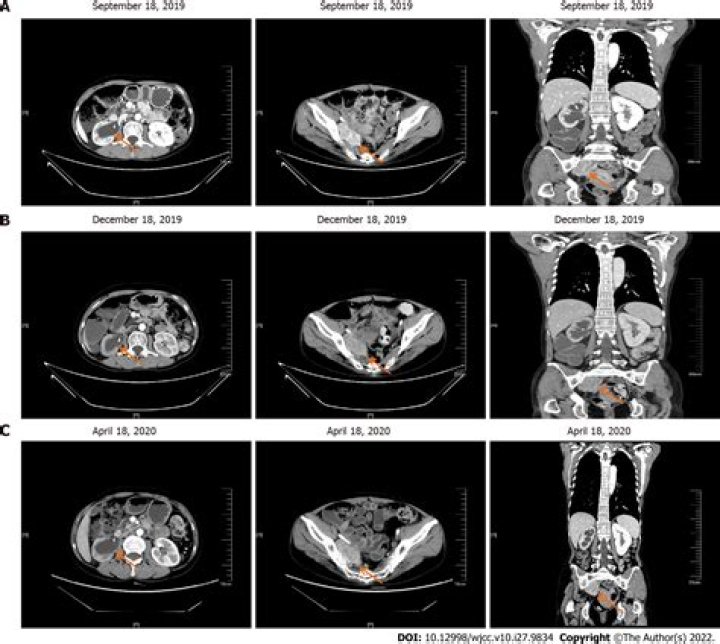

Score: 5/5 (21 votes) An ultrasound may show worms in the pancreas or liver. This technology uses sound waves to create images of internal organs. CT sca...